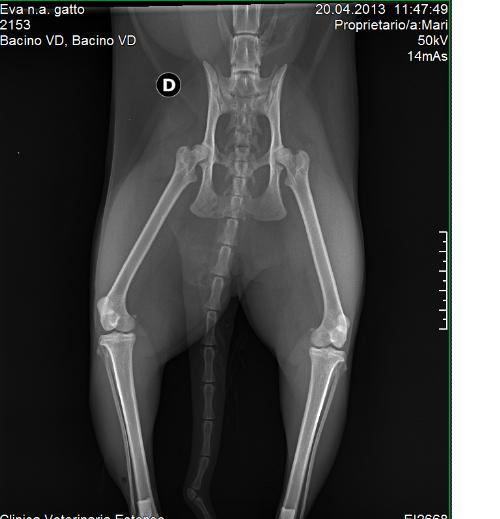

Fisioterapia Gatto Frattura Multipla Bacino Interessamento Bilaterale Del Nervo Sciatico Youtube Source: youtube.com